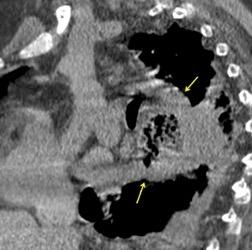

3% segregan catecolaminas.

(En el área Paravertebral +/-50%.)

Intenso realce con el contraste.

32 años .Preeclampsia a los 19. Hipertensión no controlada. Masa paravertebral sólida que se realza intensamente con afectación ósea.

Yue Y t al. Asymptomatic left posterior mediastinal functional Paraganglioma. A case report. Medicine . 2019